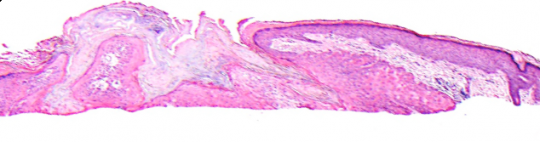

VA1: Left Forearm, Actinic Keratosis

VA1: Right Forearm, Normal